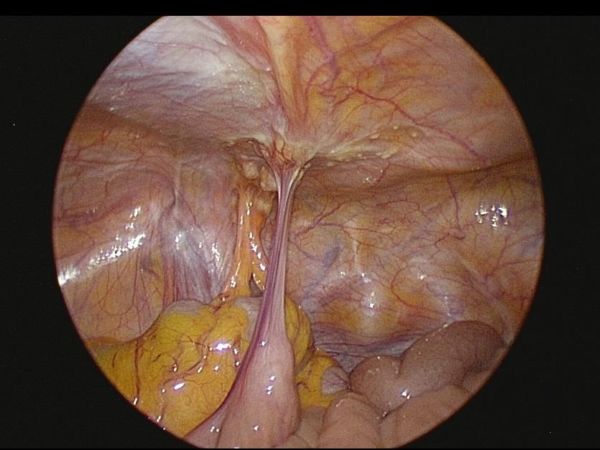

在腫瘤反應與身體條件允許下,醫療團隊進一步評估後,建議接受「腹腔高壓氣霧化學治療(PIPAC)」。此為以腹腔鏡進行的微創治療方式,將化療藥物於高壓環境中霧化,使藥物能較均勻分佈於腹腔內,作為部分腹膜癌病人之治療選項之一。陳先生完成一個療程、共三次「腹腔高壓氣霧化學治療(PIPAC)」 後,臨床症狀與檢查結果顯示病情獲得控制,相關評估指標亦呈現改善趨勢。

後續在審慎評估風險與效益後,醫療團隊為陳先生安排腫瘤減積手術(CRS),並合併術中腹腔溫熱化學治療(HIPEC)。手術過程中,醫師清除腹腔內可見病竈,並以溫熱化療藥物進行腹腔循環灌注,期望降低殘留腫瘤負荷。術後恢復過程順利,並持續接受門診追蹤與治療照護。陳先生食慾、體力與日常活動能力逐步改善,生活品質也獲得提升。家屬表示,感謝醫療團隊在治療過程中提供清楚說明與完整照護,讓全家能安心面對治療歷程。